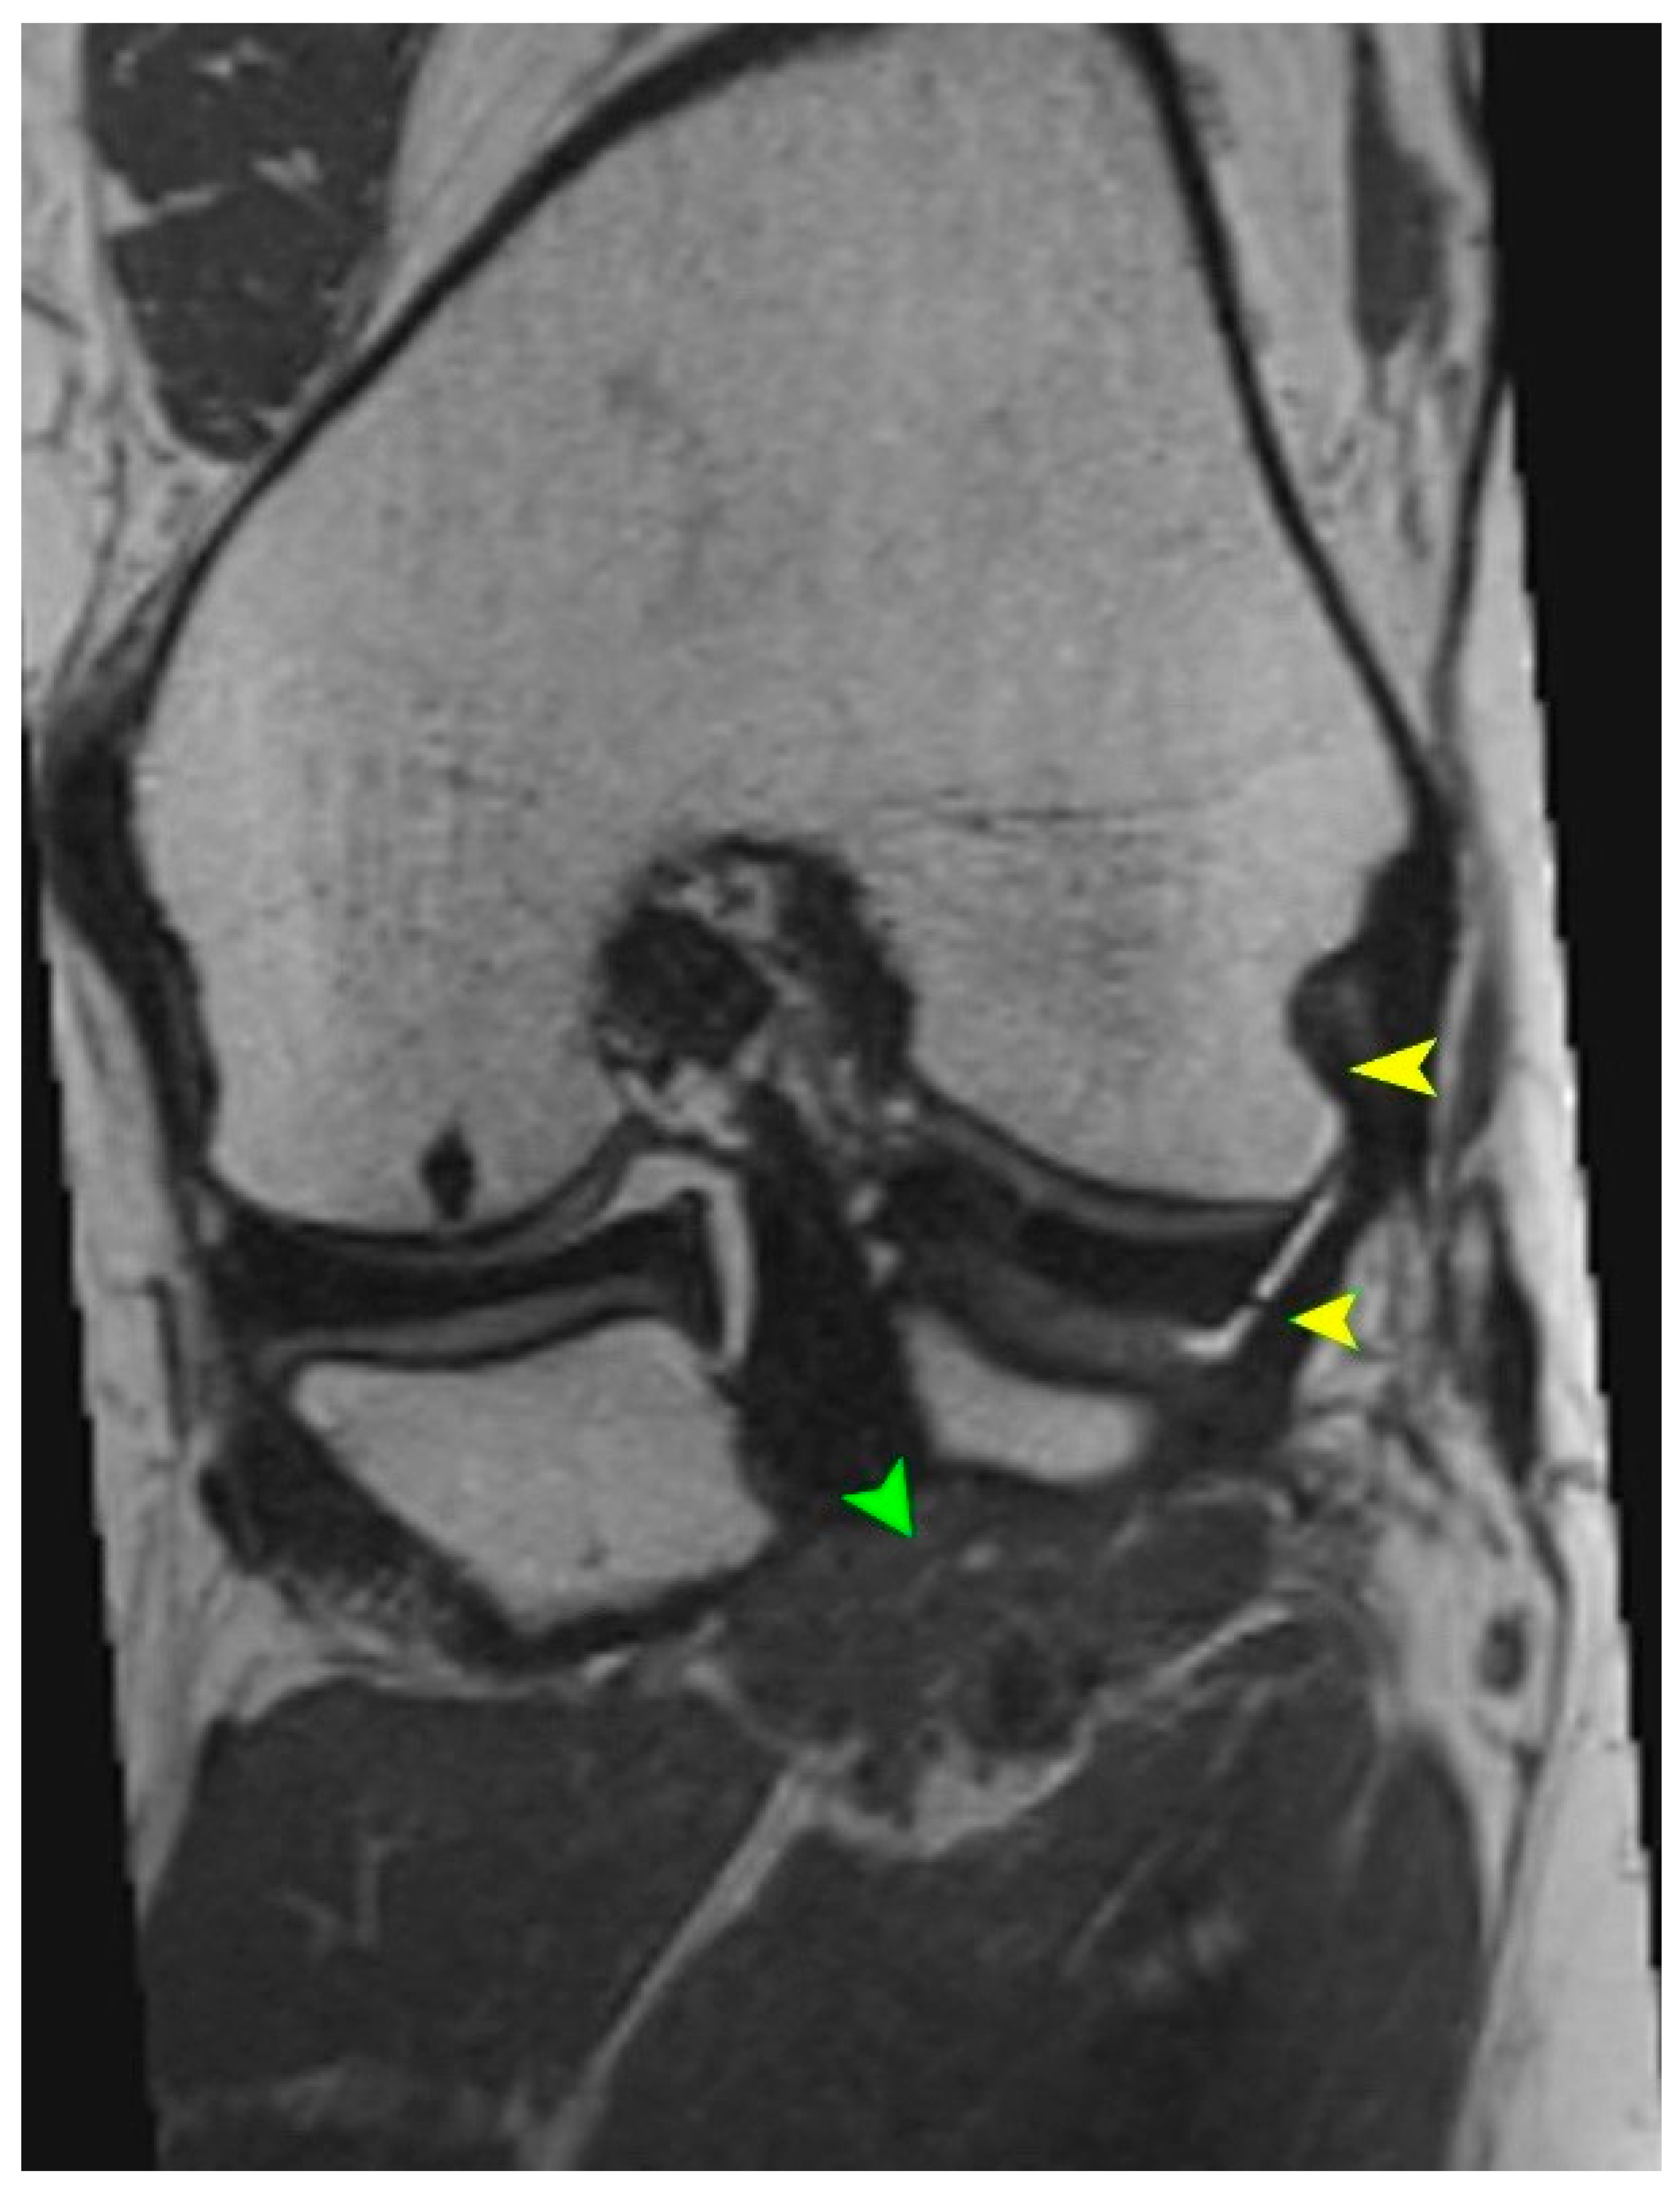

5.2. Magnetic Resonance Imaging (MRI)

5.3. High-Resolution Ultrasound (US)

- Advanced imaging (MRI and high-resolution ultrasound) should include targeted assessment of the PT, particularly for patients with lateral or rotational knee instability or for preoperative planning for complex reconstructions.